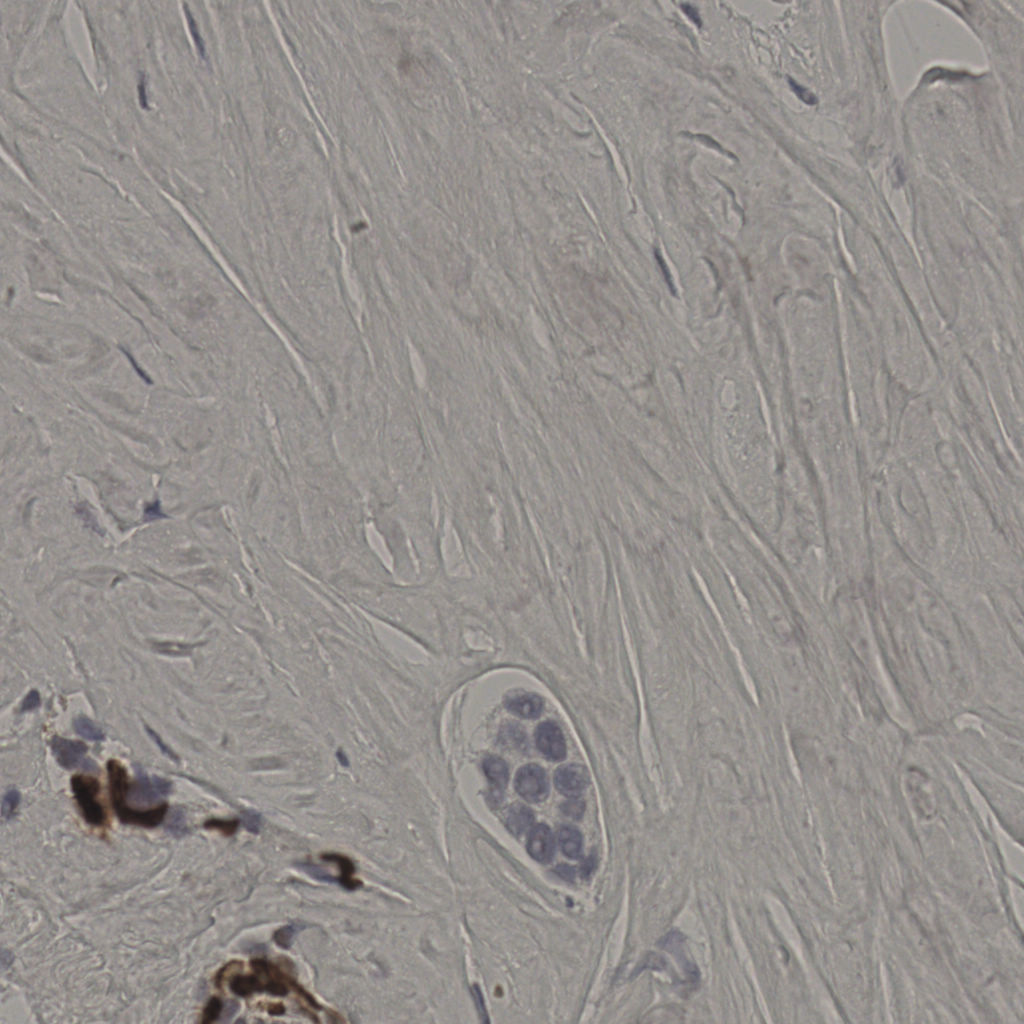

17.75%

Ki67 指数

阴 7986

阳 1723

切片统计

总切片

2640

有效

412

已标记

412

有效率

16%